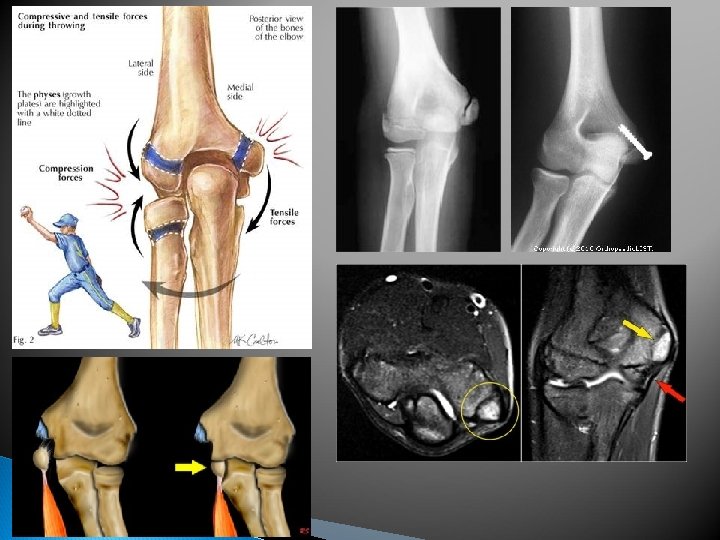

Ulnar Collateral Ligament Sprain Cause: Hyperextension or excessive Valgus Force. This injury usually occurs during the cocking phase of the throwing motion Signs & Symptoms: Pain, Care: Ice, compression Instability, numbness & tingling, Point tenderness over the UCL sleeve, sling, rest. Follow up with a physician for evaluation, x-ray & MRI if necessary. Surgery is required to repair the injury. Recovery after surgery is approximately 9 months During rehabilitation throwing is restricted for the first 12 weeks. After 12 weeks, throwing is controlled by limiting & gradually progressing the number of throws per day

UCL Sprain Ulnar Collateral Ligament

Stress on the UCL

Medial Epicondylitis Cause: repetitive wrist flexion & elbow flexion. AKA as Little Leaguer’s elbow, Pitcher’s Elbow & Golfer’s Elbow Signs & Symptoms: Point tenderness, Swelling over medial epicondyle, Pain with wrist Flexion, Pain radiating down the arm, aching, weakness, point tenderness over medial epicondyle Care: Rest, NSAIDs, Ice, Range of Motion exs, stretching, strengthening, Counterforce brace. Return to play through throwing program if athlete is an overhead thrower, Severe cases may require splinting

Medial Epicondylitis